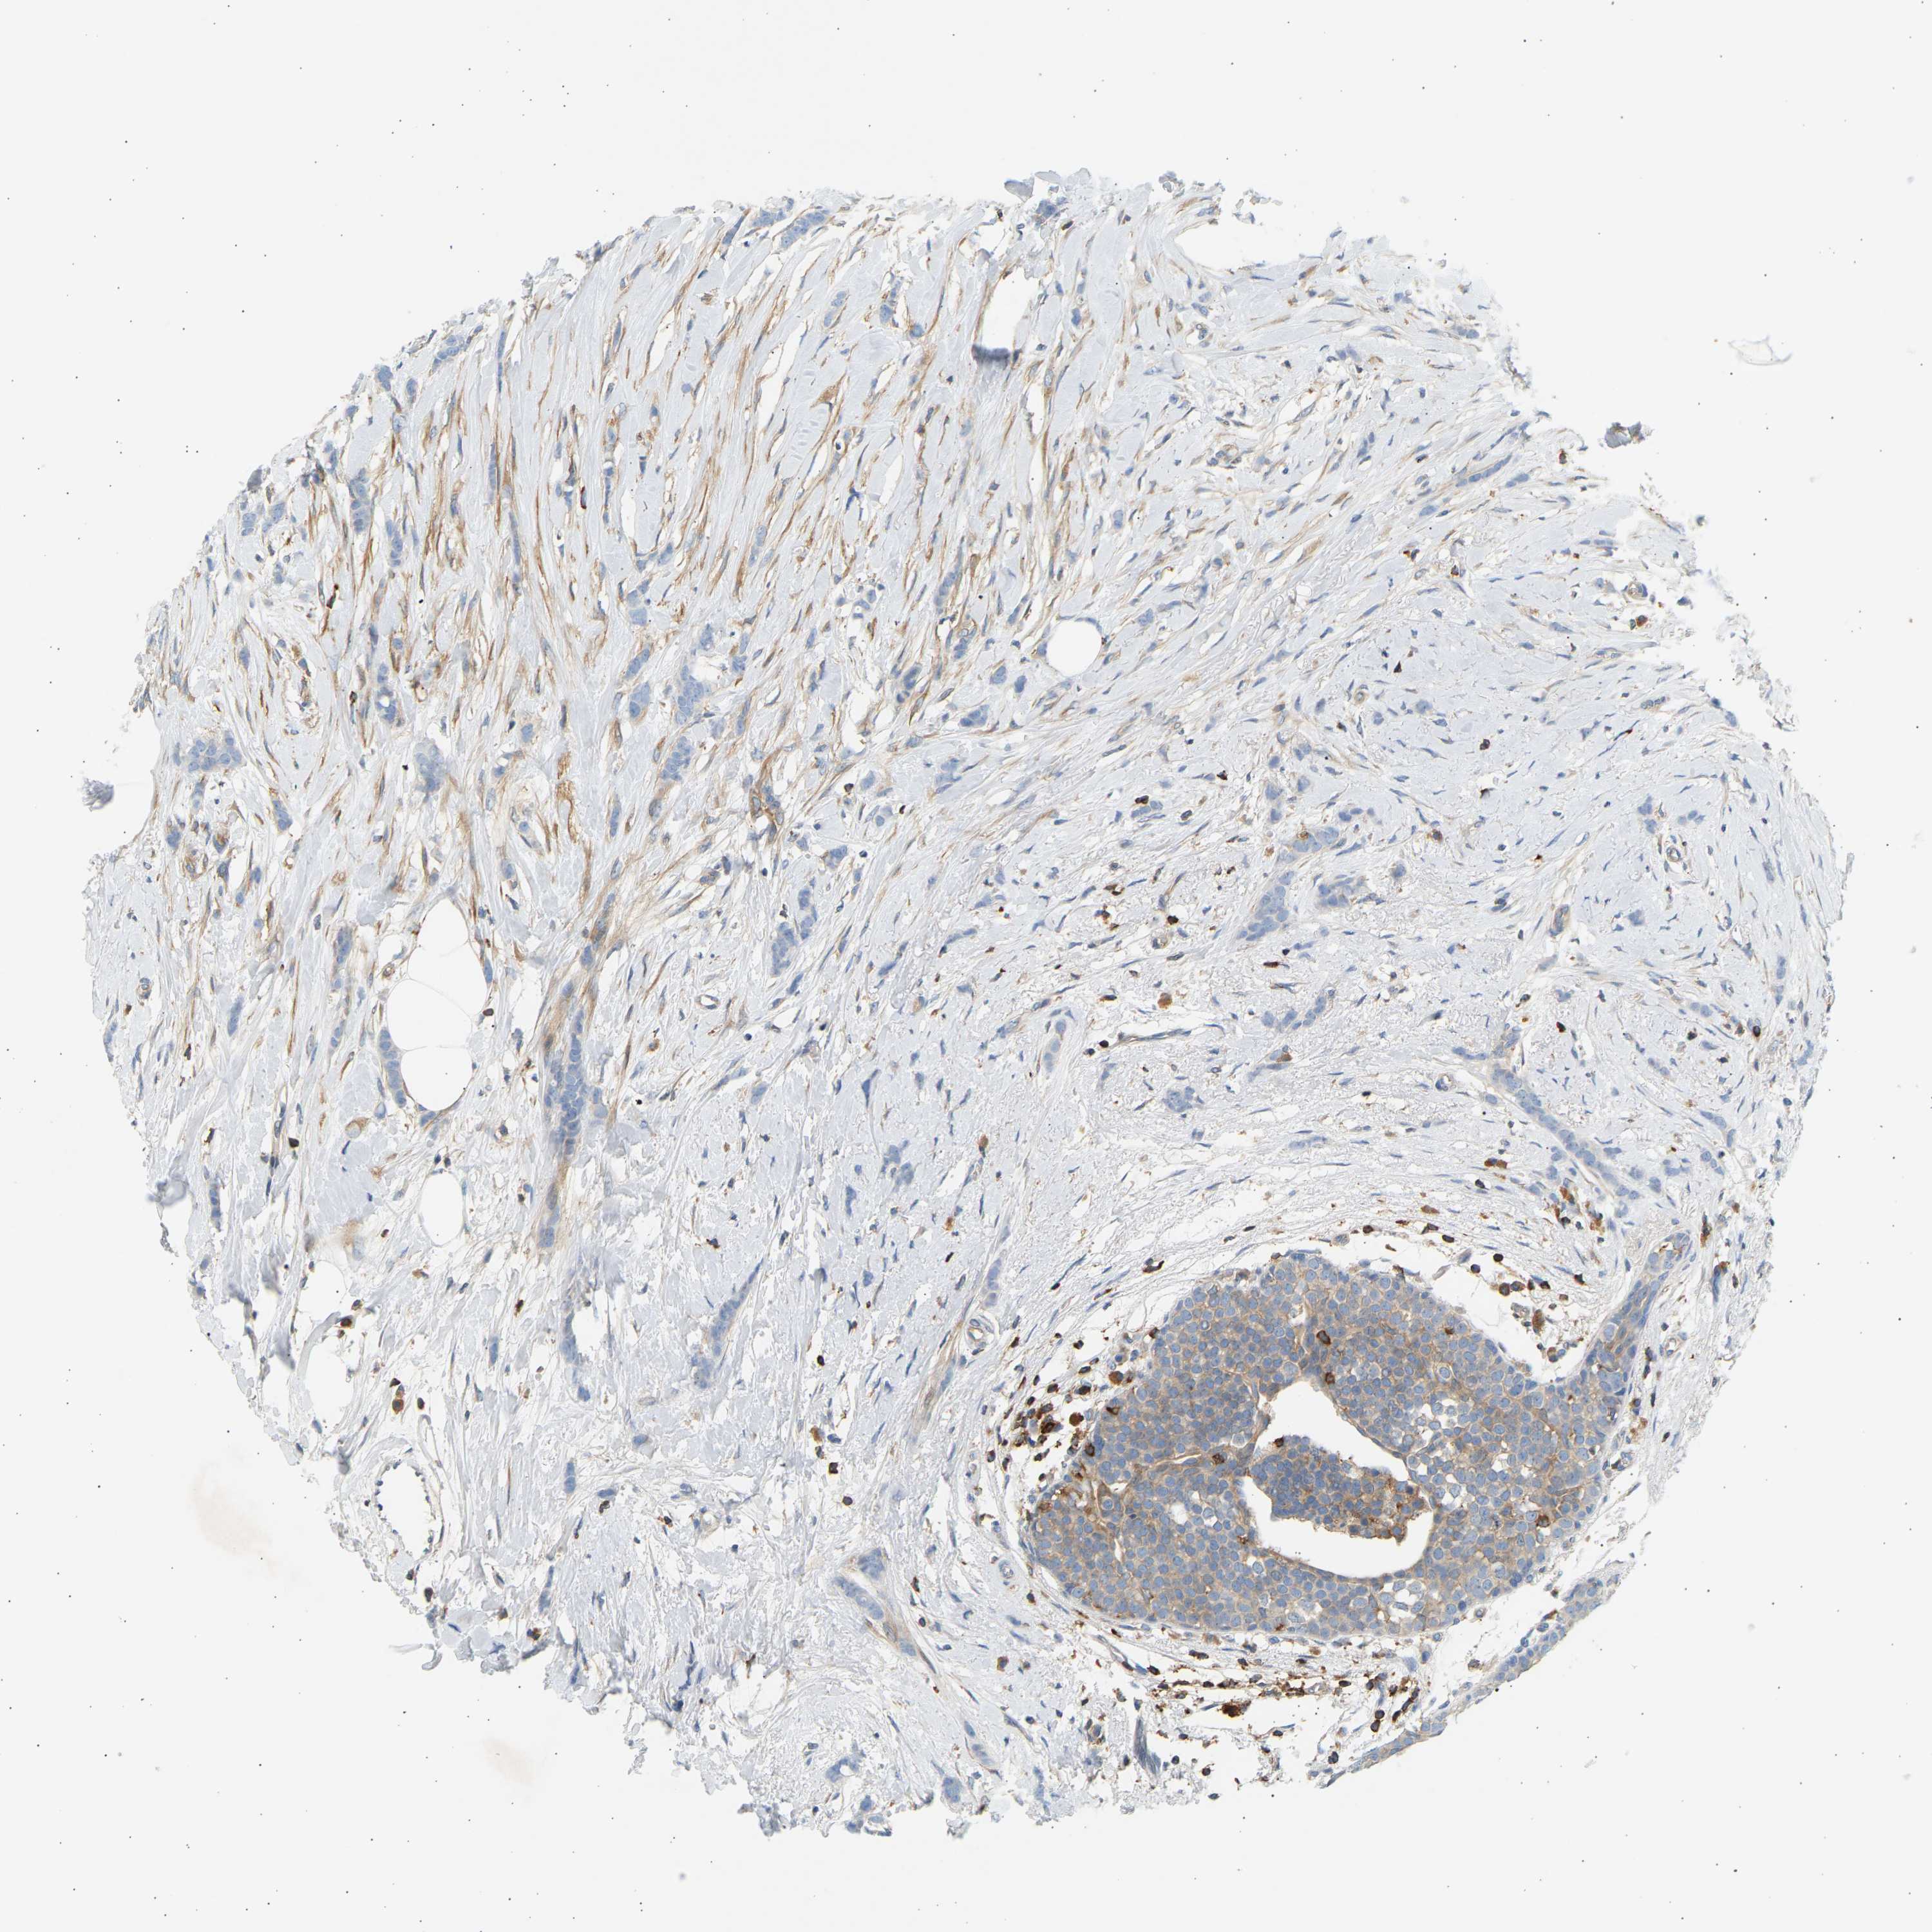

BRCA TCGA BRCA VALIDATION PROTEIN EXPRESSION

TCGA RNA samplesi

RNA-seq data is reported as average FPKM (number Fragments Per Kilobase of exon per Million reads), generated by the The Cancer Genome Atlas (TCGA) .

Normal distribution across the dataset is visualized with box plots, shown as median and 25th and 75th percentiles. Points are displayed as outliers if they are above or below 1.5 times the interquartile range. FPKM values of the individual samples are presented next to the box plot.

Average pTPM 22.5

Number of samples 1022